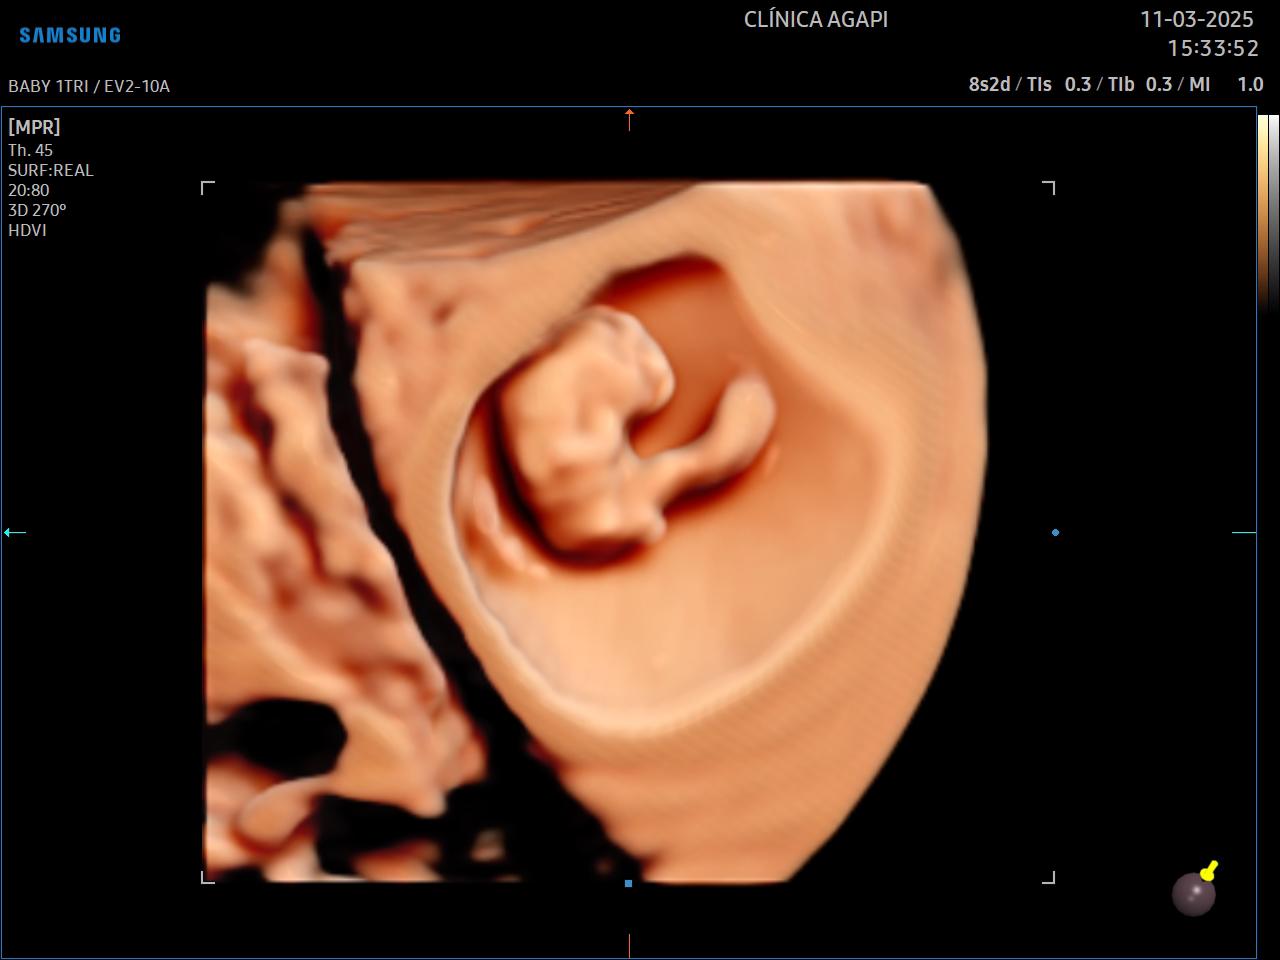

O 3D é realizado com um transdutor especial que reconstrói a superfície adquirida em uma imagem de 3 dimensões, estática. Já o 4D permite visualizar essas imagens com movimento do bebê em tempo real. Com a tecnologia HD live temos a cor do feto que dá a impressão da cor da pele.

A capacidade de aquisição de uma boa imagem tridimensional (3D/4D) depende de vários fatores, dentre eles: quantidade de líquido amniótico, posição fetal, inserção placentária, espessura do tecido celular subcutâneo materno, número de fetos, padrão de movimentação fetal durante o exame, dentre outros fatores que devem sempre ser individualizados.

Aqui na AGAPI, em qualquer exame - e se o bebê colaborar, sempre vamos fazer esses registros incríveis que a mamãe tanto ama.